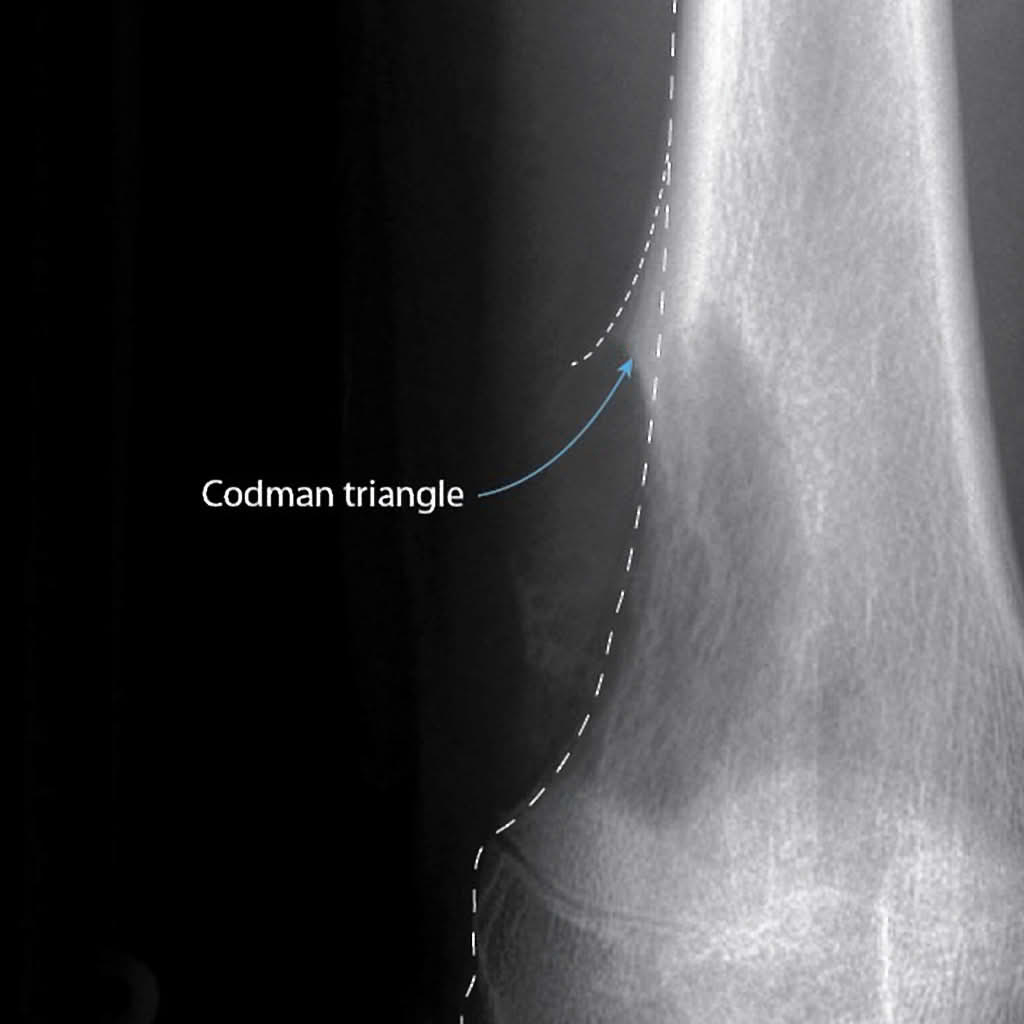

2) 방사선 소견

파괴적이며 혼합성 용해성(lucent)과 골형성(blastic) 병변이 특징적이다

종양이 골막을 들어올리며 Codman 삼각형(Codman triangle)이라는 특징적 방사선 소견을 보인다.

Codman triangle, Wikimedia Commons